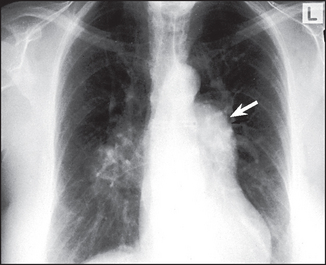

Figure 8.9 Atrial septal defect (ASD) The most important thing to recognise is that there is pulmonary plethora indicating a left-to-right shunt. Left-to-right shunts occur in ASD, ventricular septal defect (VSD) and patent ductus arteriosus (PDA). The shunted flow causes enlargement of the main pulmonary artery and its branches. The right hilum is enlarged because of the very dilated right pulmonary artery. The left hilum is hidden by the very dilated main pulmonary artery (arrow). The ascending aorta is small (in contrast to its enlargement in PDA). The left atrium and ventricle are not enlarged, as they are in VSD and PDA.